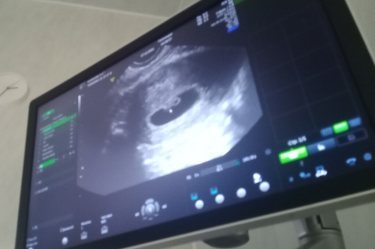

Сегодня наконец-то добралась до кабинета узи, хотя врач смотрел, но беременности не нашел, но час назад на мониторе узи я увидела долгожданную картинку😍😍 не могу поверит что это моё... У меня вопрос к вам, какие анализы должен сдать будущий папа? Знаю что анализ на спид и вич